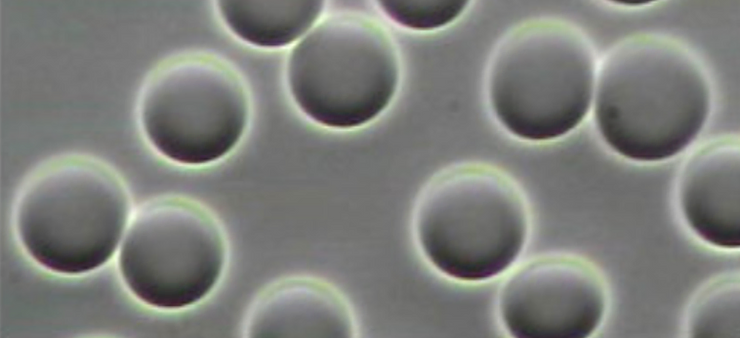

In order for the red blood cells to remove acidic metabolic waste and to pick up life giving oxygen they must pass through the pulmonary vein and then into the capillary pools. If the red blood cells are in pathological coagulation or aggregation there is no way to enter. Why? Because the entry into the capillary venules that branch off from the pulmonary vein measure 3 to 5 microns (1 micron is 1/25,000 of an inch – See Micrograph 1) and a single red blood cell measures 7 microns which makes it impossible for the red blood cell to enter the capillary venules if they are aggregated or coagulated into groups of red blood cells! [4]

Pathological blood coagulation or disseminated intravascular blood coagulation (DIC) inside the pulmonary vein will prevent the free passage of red blood cells into the alveoli of the lungs via the pulmonary capillaries. {See Phase Contrast Micrograph 3 and 4) Erythrocytes or red blood cells must go into the pulmonary capillaries single file. If they cannot pass into the pulmonary capillaries of the lung to the alveoli this will cause oxygen deprivation that leads to red blood cell hypoxia (carbon dioxide poisoning) degeneration, genetic mutation, sepsis and sudden death.[6][7][8]

What Should Healthy Red Blood Cells Look Like?

Normal healthy red blood cells should be even in color, even in shape and finally even in size. (Phase Contrast Micrograph 5) Keeping the red bloods cells separated is critical so they can enter the pulmonary capillaries that lead to the alveolus sacs where the red blood cells eliminates acidic waste of carbon dioxide and lactic acid and adsorb and then absorb life-giving oxygen into the hemoglobin molecule. The following phase contrast micrograph is what normal healthy red blood cells should look like![12]